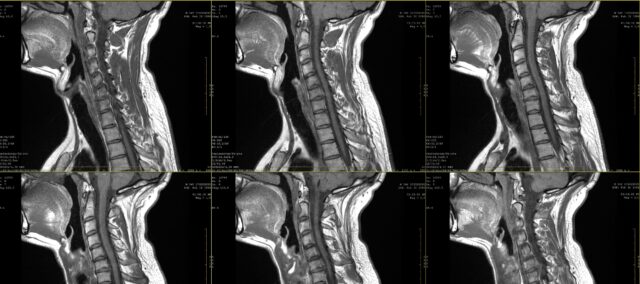

Na escola, você certamente aprendeu sobre desenhos de dor para dor radicular. Entretanto, já na primeira década do século XXI, ficou claro que a dor radicular não segue necessariamente uma distribuição dermatomal. Este estudo quis examinar mais de perto a concordância entre a inspeção visual de desenhos de dor radicular, conforme observado pelos pacientes, e a RM. Na prática, muitas vezes o paciente expressa suas queixas e isso pode ser complementado com um desenho da dor. Quando há suspeita de dor radicular, geralmente são prescritos exames médicos de imagem para determinar a raiz nervosa afetada e a extensão do possível envolvimento da raiz nervosa. Embora isso faça parte da prática rotineira em muitos casos, não sabemos até que ponto existe concordância entre esses desenhos de dor e a raiz nervosa afetada, conforme determinado pela RM. Neste estudo, Marco et al. (2023) compararam desenhos de dor radicular e achados de RM.

Para investigar a concordância entre os desenhos de dor radicular e os achados da RM, este estudo incluiu participantes com histórico de dor persistente de dois meses, que foram diagnosticados com radiculopatia cervical na RM. Esse diagnóstico foi feito por um neurocirurgião com base em informações clínicas e nos achados da RM avaliados por um radiologista.